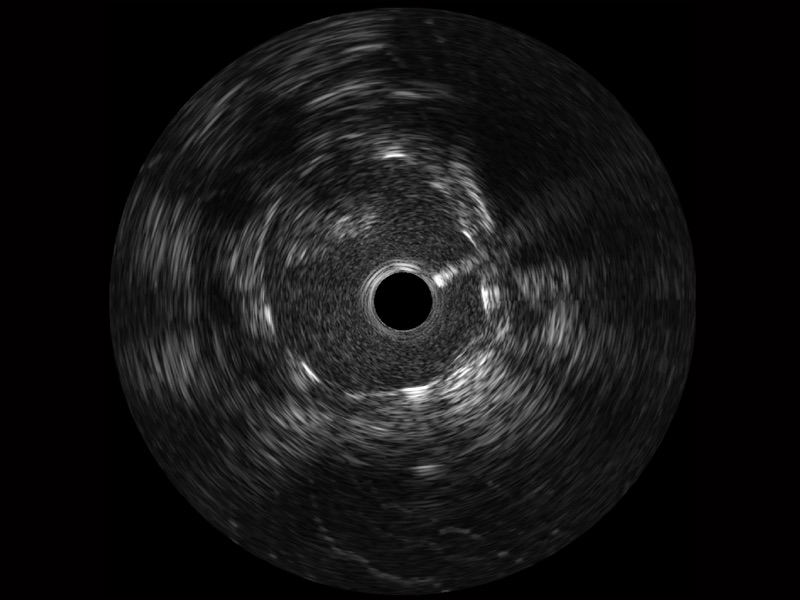

传统IVUS图像

对比传统IVUS导管成像,16877太阳集团宽频IVUS图像的近场支架梁显影更细腻,远场中膜外血管仍清晰可辨,兼顾远中近,兼顾分辨力与穿透深度